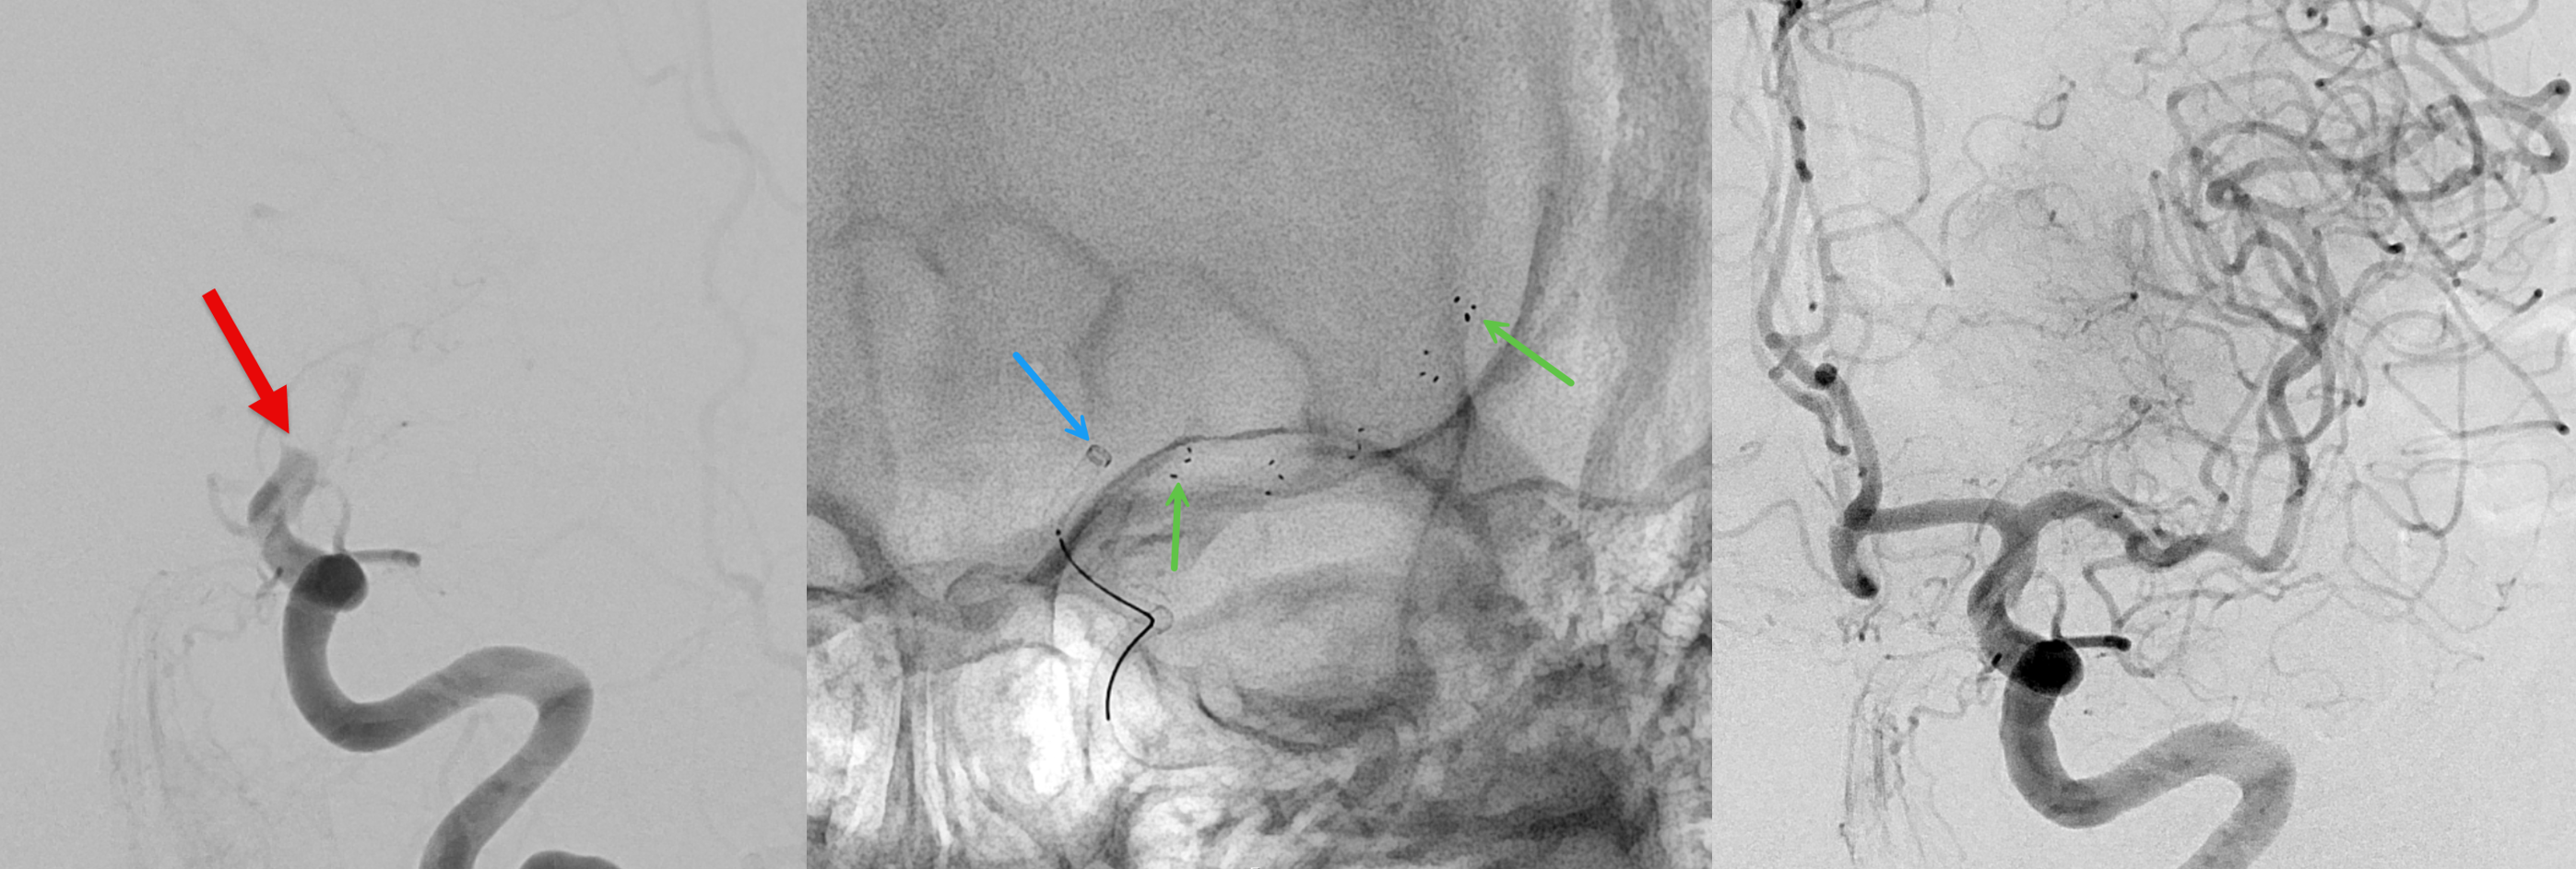

Ein wichtiger Meilenstein in der Neuro-Intervention war die Einführung der sogenannten ablösbaren Platinspiralen ("Coils") Anfang der 1990er Jahre. Diese Innovation ermöglichte erstmals den minimal-invasiven Verschluss von intrakraniellen Aneurysmen (krankhafte Gefässerweiterungen im Gehirn). Damit veränderte sich die Behandlung von Blutungen im Gehirn (hämorrhagische Pathologien) grundlegend. Die Technik entwickelt sich kontinuierlich weiter: Moderne Werkzeuge wie Remodelling-Ballons, Stents und Flow-Diverter ermöglichen heute die effektive Versorgung selbst komplexester Aneurysmen.